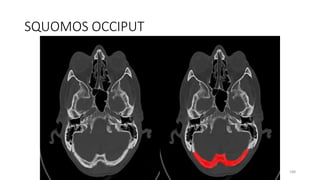

SQUOMOS OCCIPUT

188

203

SQUAMO OCCIPUT

215

SQUAMOUS OCCIPITO

225

SQUAMO- OCCIPITO

234